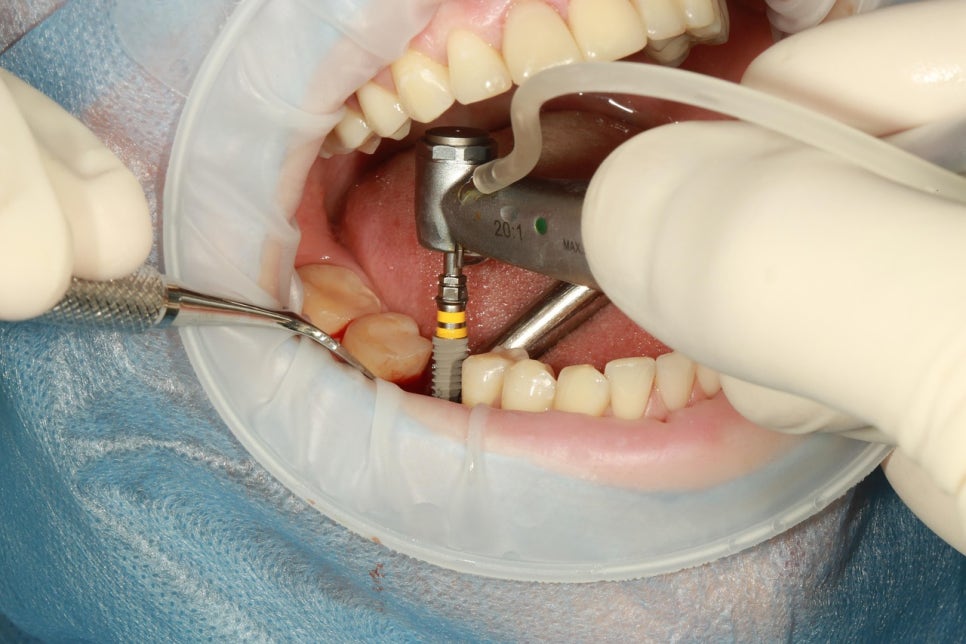

[스마일디 임플란트 사례 중 일부]

치료기간: 23.12.25일-24.06.28 (약 6개월)

진행한 치료: 발치 후 염증치료, 골이식과 임플란트2개 식립후 브릿지

치료기간: 24.11.03일-24.12.03(약 1개월)

진행한 치료: 발치 후 임플란트

*치료 전후 사진은 환자의 동의하에 게재하였으며, 동일한 환경과 조건에서 촬영된 전후 사진입니다.